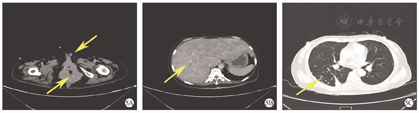

对这11例患者随访至2022年3月31日,随访时间为3~34个月。其中,2例患者(No.2、9)分别为FIGO ⅢC2期及ⅢB期(No.9),均死于DEC。No.2患者术后接受放、化疗6个月后,出现腹腔内广泛转移导致肠梗阻而死亡,OS期为9个月。No.9患者于术后1个月出现高钙血症及肿瘤广泛转移(阴道、直肠、肛管、膀胱后壁、阴阜、肝、肾上腺、双肺)(图5),阴道肿块经穿刺活组织病理学检查结果证实为UEC转移后,2个月死亡,OS期为3个月。6例(No.1、4~6、10~11)FIGO Ⅰ~Ⅱ期患者截至发稿均无瘤存活。目前存活的9例患者(No.1、3~8、10~11)中,OS期最长者已达34个月,中位OS期为10.5个月。

注:DEC为去分化子宫内膜癌